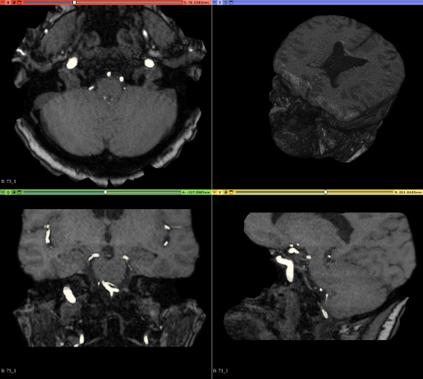

We hereby present a full synthetic model, able to mimic the various constituents of the cerebral vascular tree: the cerebral arteries, the bifurcations and the intracranial aneurysms. By building this model, our goal was to provide a substantial dataset of brain arteries which could be used by a 3D Convolutional Neural Network (CNN) to either segment or detect/recognize various vascular diseases (such as artery dissection/thrombosis) or even some portions of the cerebral vasculature, such as the bifurcations or aneurysms. In this study, we will particularly focus on Intra-Cranial Aneurysm (ICA) detection and segmentation. The cerebral aneurysms most often occur on a particular structure of the vascular tree named the Circle of Willis. Various studies have been conducted to detect and monitor the ICAs and those based on Deep Learning (DL) achieve the best performances. Specifically, in this work, we propose a full synthetic 3D model able to mimic the brain vasculature as acquired by Magnetic Resonance Angiography (MRA), and more particularly the Time Of Flight (TOF) principle. Among the various MRI modalities, the MRA-TOF allows to have a relatively good rendering of the blood vessels and is non-invasive (no contrast liquid injection). Our model has been designed to simultaneously mimic the arteries geometry, the ICA shape and the background noise. The geometry of the vascular tree is modeled thanks to an interpolation with 3D Spline functions, and the statistical properties of the background MRI noise is collected from MRA acquisitions and reproduced within the model. In this work, we thoroughly describe the synthetic vasculature model, we build up a neural network designed for ICA segmentation and detection, and finally, we carry out an in-depth evaluation of the performance gap gained thanks to the synthetic model data augmentation.